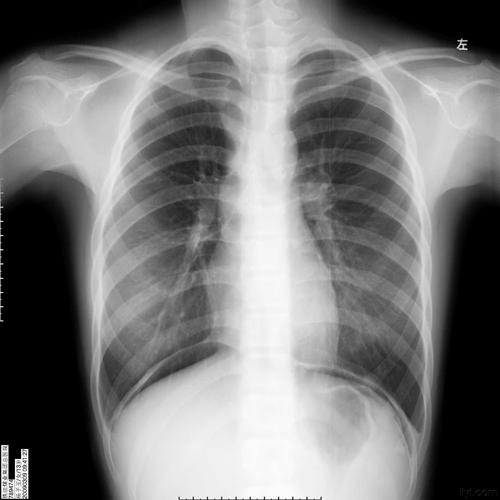

(腹腔积气,气腹)消化道溃疡内镜检查后,腹部疼痛.